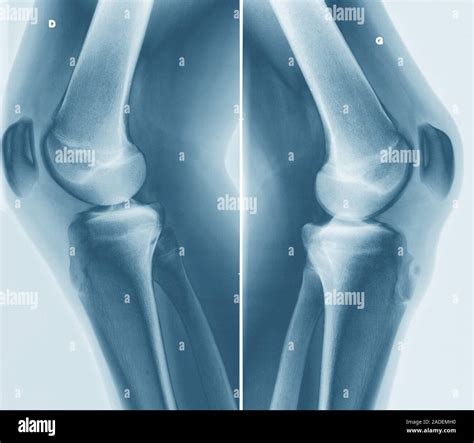

Sometimes, knee pain in teenagers can stem from issues that are more concerning than a simple growth-related inflammation. An Osgood Schlatter X ray is vital for differential diagnosis. Here is a brief comparison of how imaging helps distinguish common knee issues:

• Sinding-Larsen-Johansson Syndrome: Similar to Osgood-Schlatter, but the pain occurs at the bottom of the kneecap rather than the tibial tubercle.

• Patellar Tendonitis: This is inflammation of the tendon itself, which usually does not show significant bone changes on an X-ray.

• Osteochondritis Dissecans: This involves damage to the cartilage and bone surface within the joint, which is often visible on X-rays as a loose fragment inside the joint space.